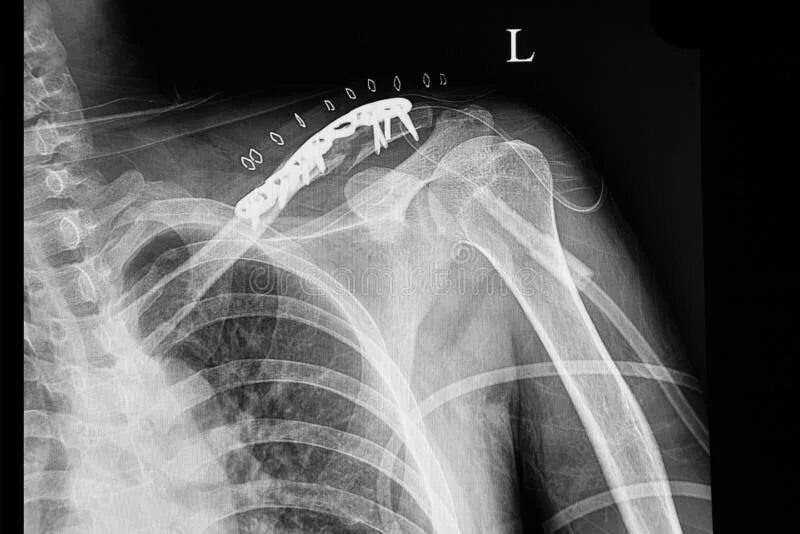

Метастазы в ключице